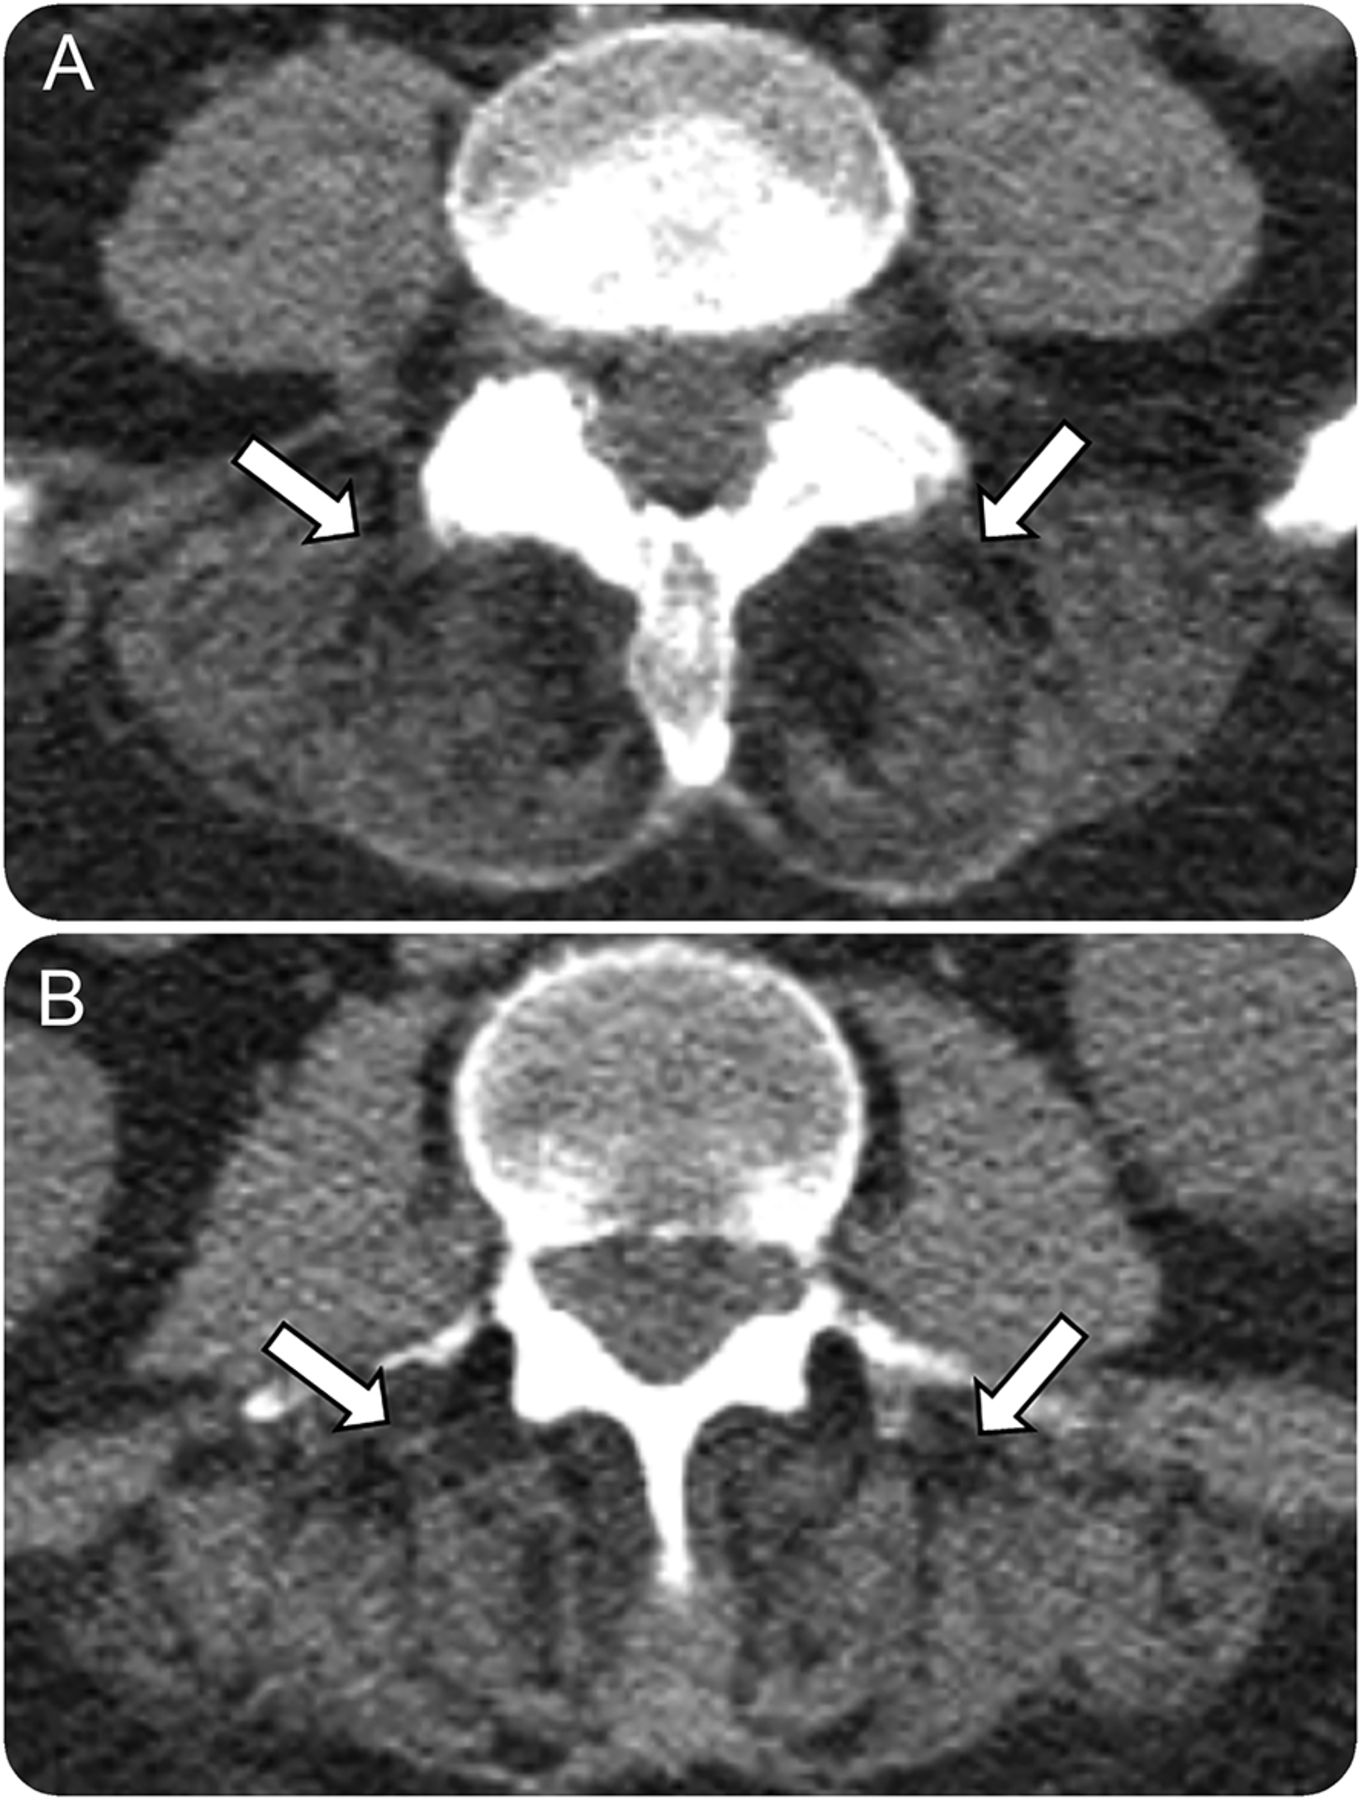

历史、检查和肌电图研究结果指向一个痛的过程。没有观察到束状或大型电机单元,使运动神经元疾病的可能性。条件可以是收购或继承。当考虑收购了肌肉疾病,药物使用信息,代谢障碍,重要的疾病,和有毒接触是至关重要的。然而,我们这些危险因素的调查是负面的。CK和ESR正常,基本上不含多肌炎,但包涵体肌炎仍然是一个可能的诊断。TSH和甲状旁腺素是正常,消除甲状腺功能减退和甲状旁腺功能亢进代谢性肌病的列表。存在的免疫球蛋白gλ副蛋白促使淀粉体肌病的考虑和零星的晚发性nemaline肌病(SLONM)。脊柱的CT扫描显示突出胸paraspinal肌肉脂肪变化(图1),发现经常看到肌肉疾病包括轴向肌肉组织。区分炎症、渗透、代谢和遗传的肌肉疾病,如前所述,肌肉活检。左二头肌肌肉活检显示中等纤维尺寸的变化特点是分散的小嗜碱(再生),使成角人肌内膜纤维化(萎缩)纤维与温和。一些肌肉纤维显示小密集的肌质聚合苏木精和伊红和Gomori修改三色的污渍。电子显微镜显示广泛的肌纤维混乱和丰富的胞质nemaline棒。免疫组织化学是无法证明的免疫球蛋白沉积,IgG4,或κλ轻链在肌肉纤维,尽管血管和间质远比λκ反应。历史、检查和病理结果与SLONM的诊断。9突变基因检测与nemaline肌病是负面的。